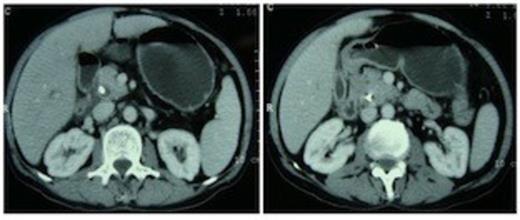

A 55 year non-diabetic male with painless progressive jaundice, pruritus and weight loss of 3 month duration was admitted in emergency with cholangitis. Investigations revealed a total leukocyte count of 17 000/cu.mm, total bilirubin: 222.3 μmol/L, direct: 136.8 μmol/L and alkaline phosphatase level: 1153 U/L. Side viewing endoscopy showed an ulceronodular growth at papilla, a papillotomy and endoscopic biliary plastic stenting was done. Neither cholangiogram nor pancreaticogram was obtained in view of cholangitis. Once his cholangitis resolved, he was referred for surgery. Pre-operative triple phase CT (computed tomography) scan of the abdomen showed a resectable ill-defined hypodense mass in the region of ampulla, the pancreatic head and uncinate were normal however the neck, body and tail of pancreas were absent (figure 1,2).

Computed tomography scan demonstrating absence of the body and tail of pancreas anterior to the splenic artery and vein.